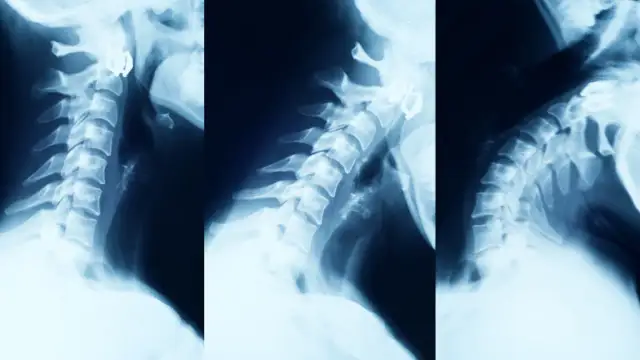

ObjawyBakteryjne zapalenie kręgosłupa: objawy, które musisz znać. Pilne!Emil Ostrowski-14 sierpnia 2025